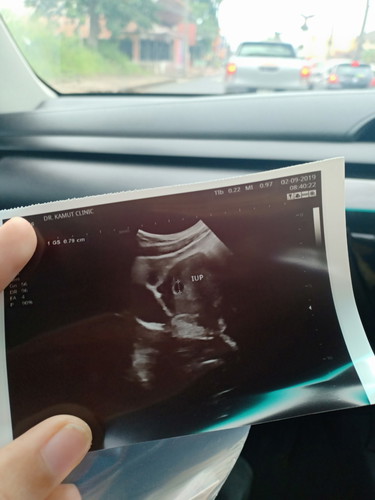

ที่กลมๆๆเล็กๆ คือถุงตั้งครรภ์ใช่ไม่ค่ะ

ช่ายคะ บำรุงเยอะๆนะคะแม่

ใช่ค่ะ

ขอบคุณค่ะ เพิ่งไปหาหมอมาค่ะ ประจำเดือนขาดไป1อาทิตย์ค่ะ